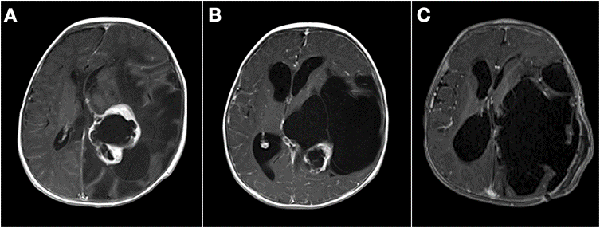

La resección parcial predominó en los grupos 1 (16 casos) y 2 (13 casos). De los 38 pacientes en los que se realizaron resecciones parciales 22 fueron lesiones supratentoriales, entre los cuales se encontraron 8 lesiones centro encefálicas (5 astrocitomas pilocíticos y pilomixoides, 1 craneofaringioma, 1 tumor embrionario indiferenciado y 1 hamartoma hipotalámico), 7 tumores de plexos coroideos (6 papilomas y 1 carcinoma de plexos coroideos) y 7 tumores hemisféricos. Por otro lado, 16 fueron lesiones infratentoriales (6 meduloblastomas, 3 teratoides rabdoides atípicos, 2 ependimomas anaplásicos, 3 astrocitomas pilocíticos, 1 pineoblastoma y 1 carcinoma de plexos coroideos). En la Figura 1 se muestran dos casos de abordajes a estos tumores.

Figura 1: Imágenes intra quirúrgicas de abordajes a tumores en SNC. A) Lesión sólido-quística cerebelosa hemisférica derecha, anatomía patológica: astrocitoma pilocítico. B) Lesión supratentorial intraventricular izquierda, anatomía patológica: papiloma de plexos coroideos.